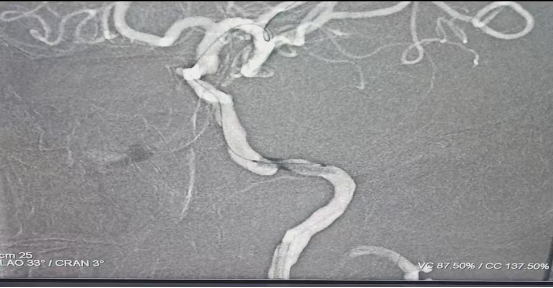

患者张晓明(化名),男性,60岁,因“反复头昏一月”来院。经全脑血管造影(DSA)精准检查,发现其颅内血管情况复杂:左侧颈内动脉C3段存在重度狭窄,血流通路严重受阻,更为棘手的是,在同一动脉的邻近眼段,还发现了一个大小约3mm*2mm的未破裂动脉瘤。此外,右侧椎动脉开口存在轻度狭窄。

手术在麻醉科吕红明主任全程监测下,采用全身麻醉方式进行。医疗团队将微导管导丝精准导航至病灶部位,在高级别栓塞保护装置护航下,对左侧颈内动脉C3段重度狭窄处实施球囊扩张并植入支架。术后造影显示,原狭窄管腔完美扩张,血流通畅性显著恢复,远端大脑血流灌注即刻改善。整个手术仅通过大腿根部一个微小穿刺点完成,术中术后患者无任何不适,术后头昏症状明显缓解。